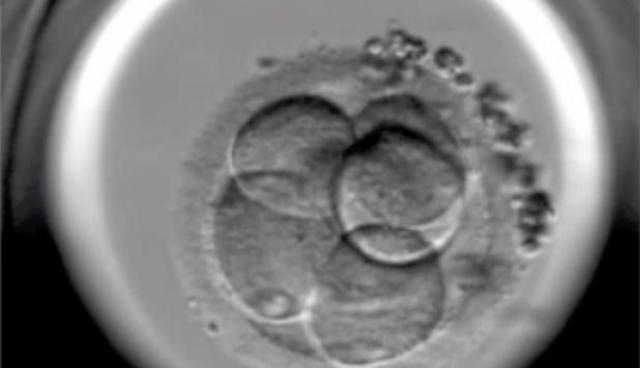

• Nacimiento in vitro

Nacimiento in vitro

En 2000 nació el primer bebé "a la carta" libre de la Anemia de Fanconi que padecía su hermana y cuyas células de cordón sirvieron para curarla. La técnica de análisis embrionario nos permite evitar el nacimiento de niños con determinadas enfermedades hereditarias.